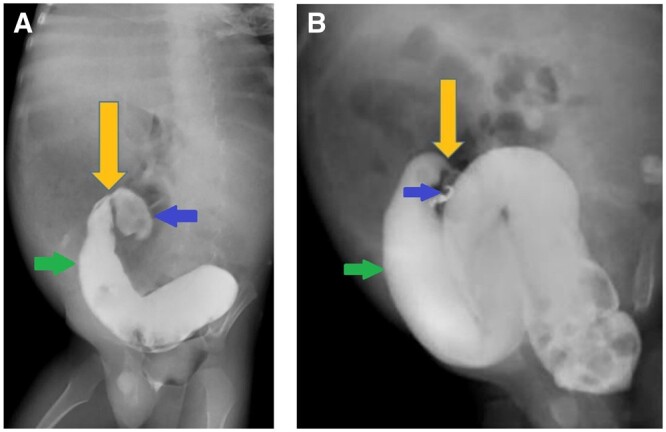

先天性乙状结肠狭窄是一种罕见的疾病,可与赫氏病相似。先天性结肠狭窄通常在出生后几周内出现。我们的病例在 2 岁时出现远端肠梗阻,并伴有慢性便秘、出生后一周内腹部逐渐胀大以及最近一周内胆汁性呕吐的病史。临床诊断为赫氏病。对比增强腹部 CT 显示肠梗阻,过渡点位于乙状结肠近端。乙状结肠近端有一短段狭窄。造影剂灌肠显示乙状结肠近端狭窄。狭窄远端肠道口径正常。手术中也发现了类似的情况。狭窄肠段存在中结肠。切除的狭窄部分在组织病理学中显示有足够的神经节细胞。

Congenital sigmoid colon stenosis is a rare entity that can mimic Hirschsprung disease. Presentation of congenital colon stenosis is usually within first few weeks of life. Our case presented with features of distal bowel obstruction at 2 years of age with the history of chronic constipation and progressive abdominal distention from first week of life and bilious vomiting for the last 1 week. Clinical diagnosis of Hirschsprung disease was made. Contrast enhanced CT abdomen showed bowel obstruction with transition point at the level of proximal sigmoid colon. There was a short segment stenosis at the level of proximal sigmoid colon. Contrast enema showed stenosis at proximal sigmoid colon. The bowel distal to stenosis was normal in calibre. Similar findings were seen during surgery. Mesocolon was present in stenosed segment of the bowel. The resected stenotic segment showed adequate ganglion cells in histopathology.